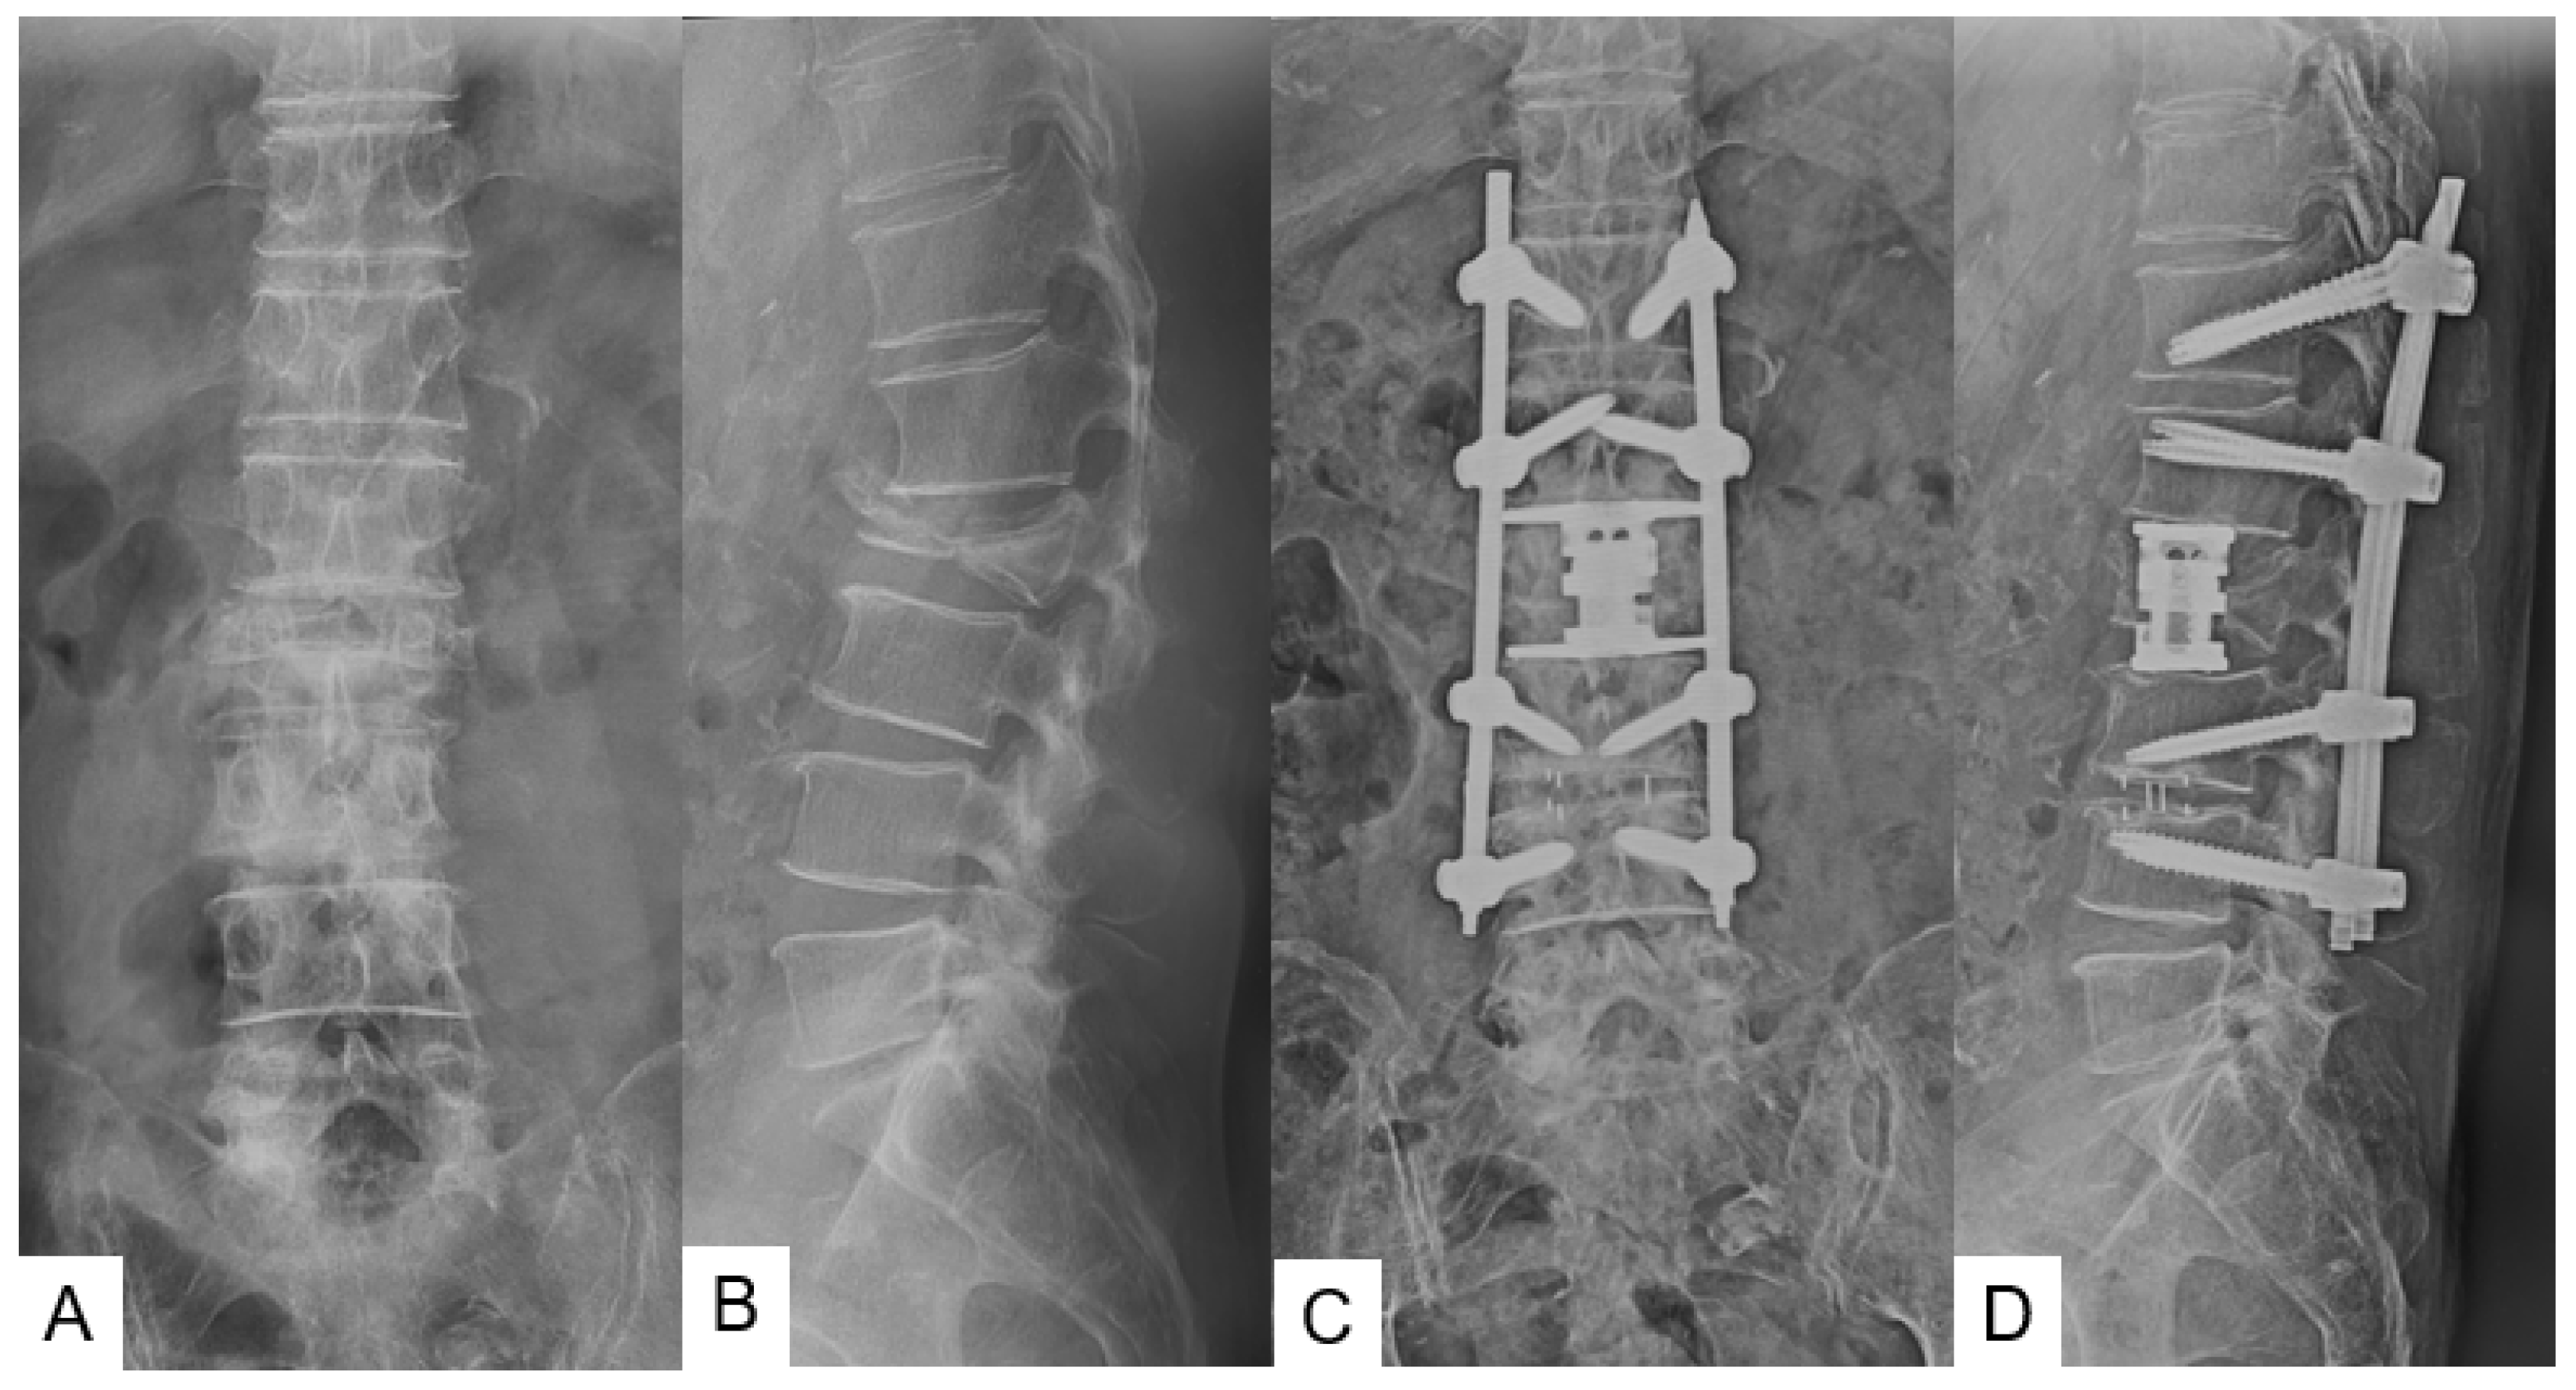

3.1. Clinical Evaluation

3.2. Radiographic Evaluation